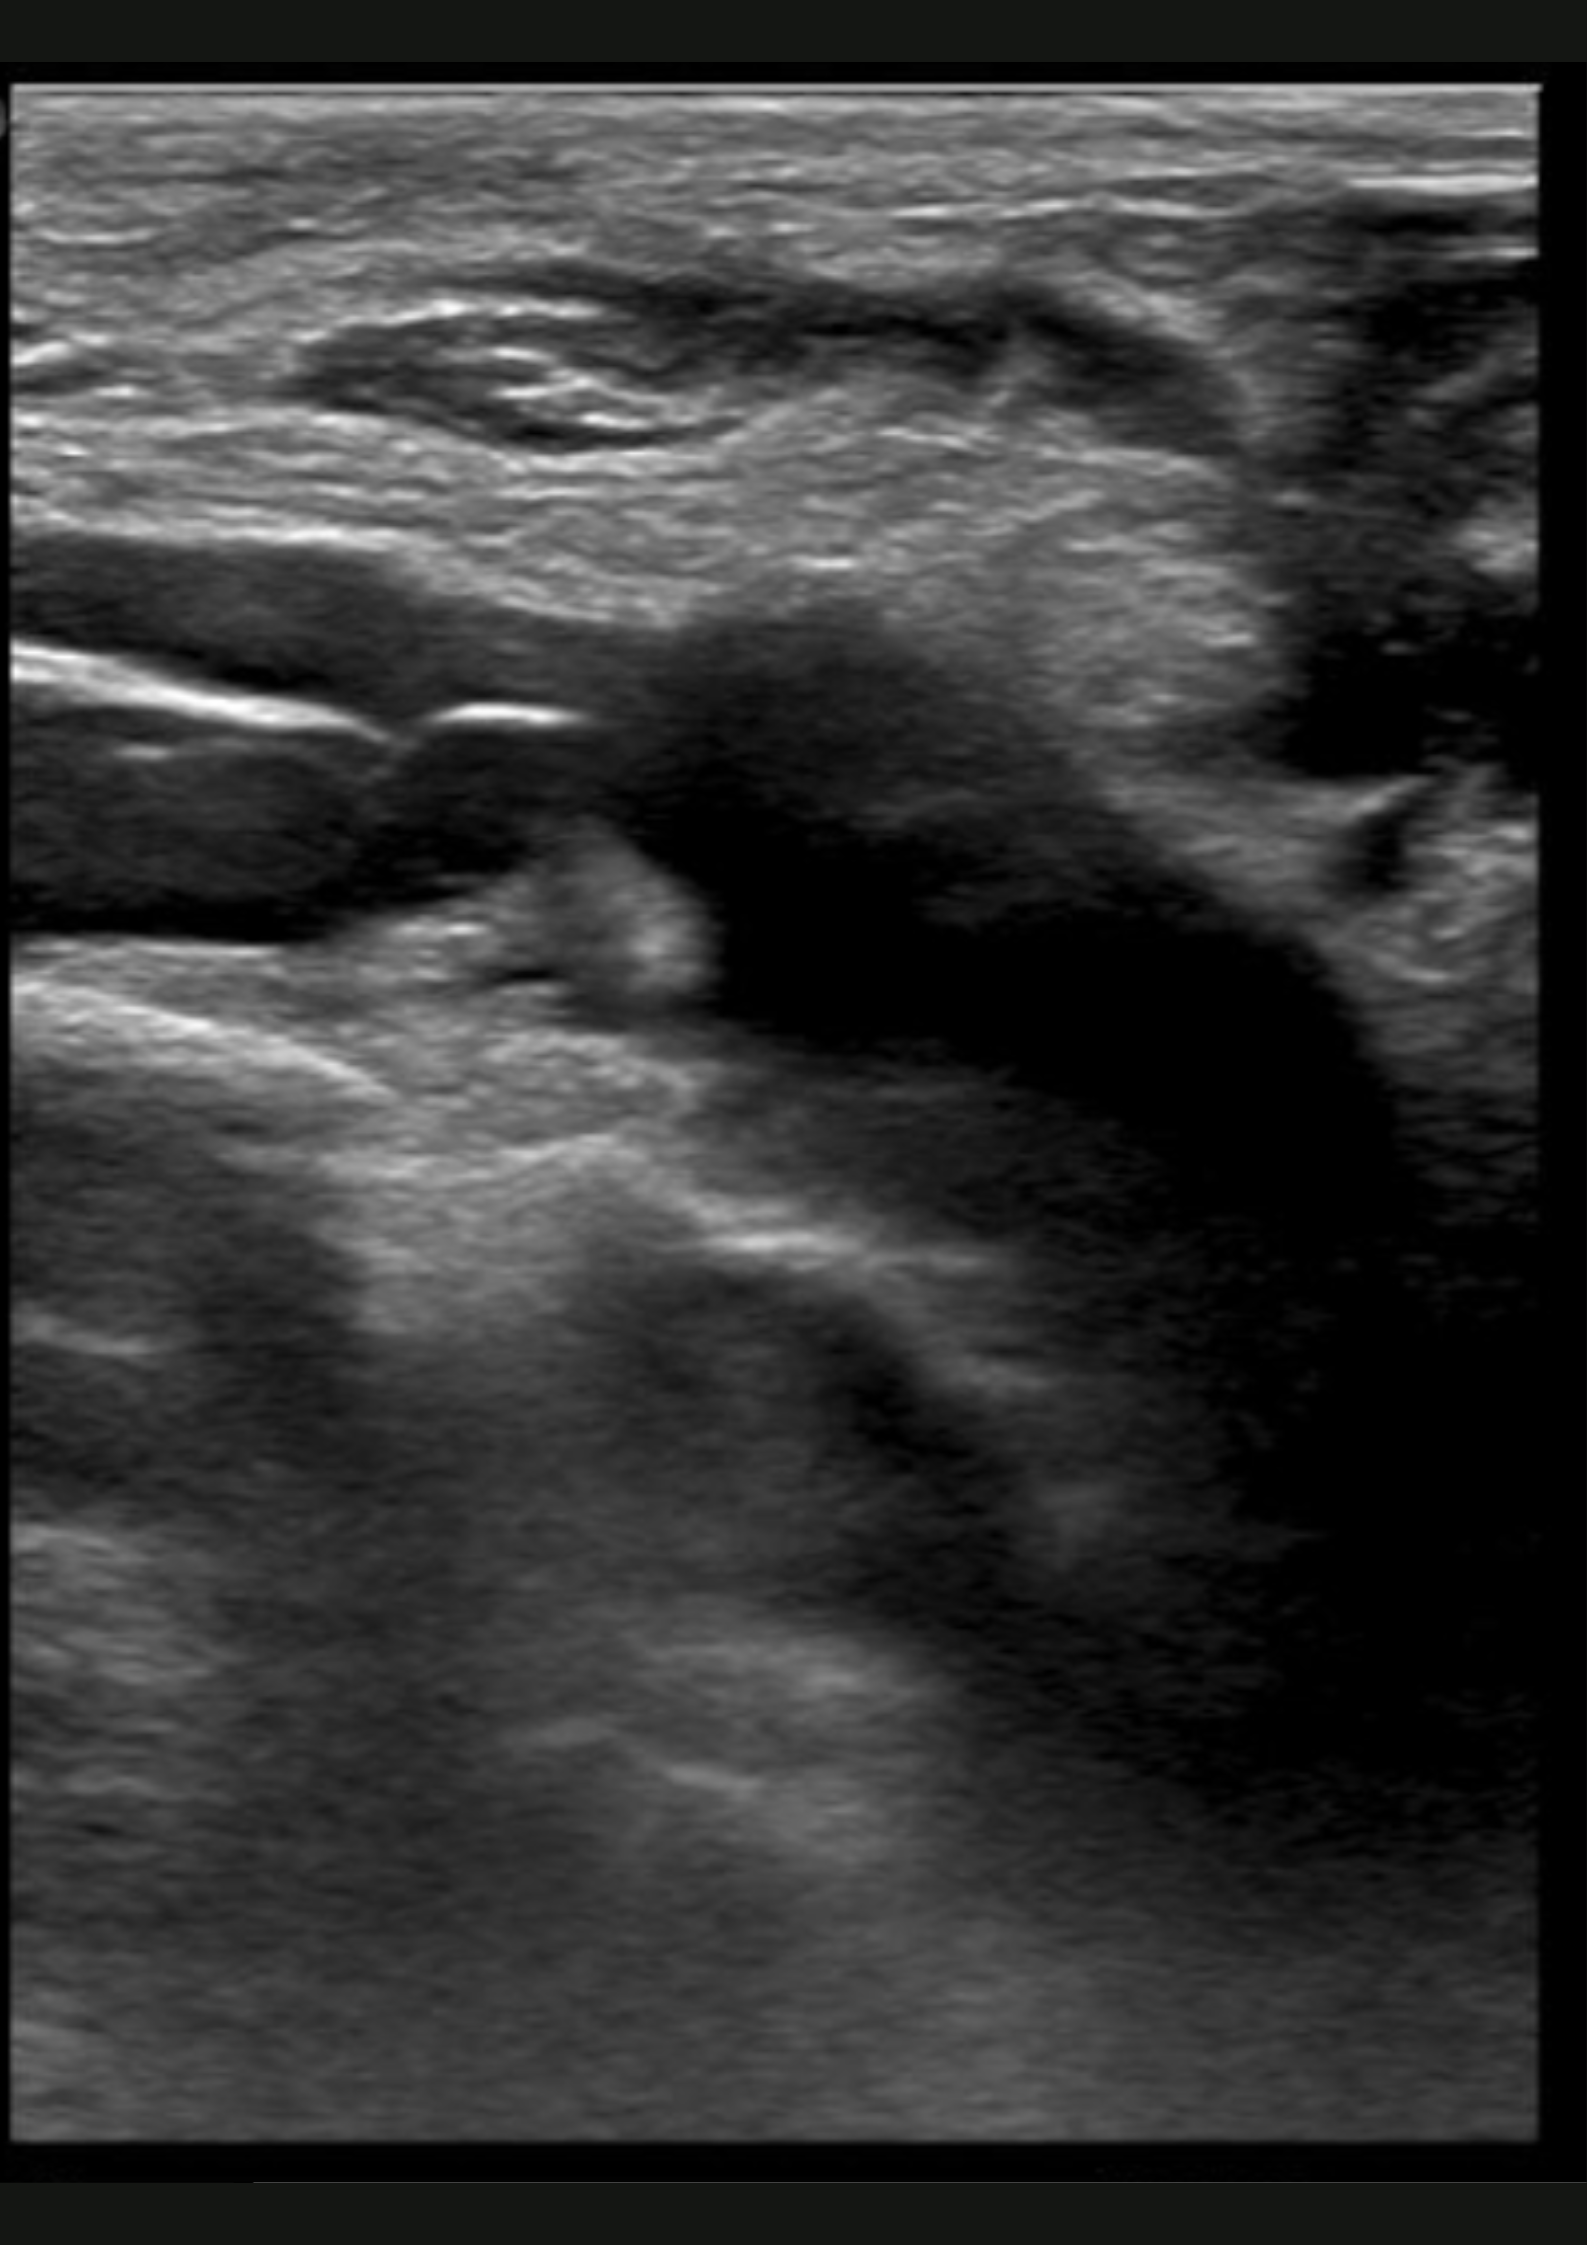

Hallazgos ecográficos

En la ecografía no apreciamos alteraciones musculares pero observamos dificultad para la compresión de la vena subclavia derecha en extensión.

Trombosis venosa profunda de sublcaiva, innominada, cefálica y yugular derecha.

Se remite a Urgencias del hospital de referencia con hallazgos de coagulación: INR 1.05, fibrinógeno 464, Dímero D 1222; y una ecografía de partes blandas que muestra una trombosis venosa de la vena subclavia derecha y vena innominada, con ligera extensión a la vena yugular derecha y cefálica derecha. Posteriormente, se inicia heparina subcutánea y se realiza fibrinolisis con perfusión de urokinasa. En el estudio de coagulación posterior se determinó una hiperhomocisteinemia y probable síndrome antifosfolípido (Paget-Schroetter).